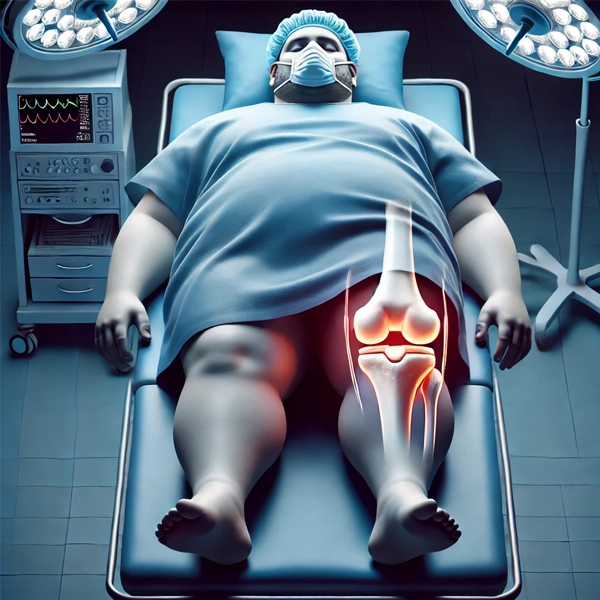

خطرات بیهوشی و عوارض جراحی در بیماران دارای اضافه وزن

افراد با اضافه وزن یا چاقی در معرض خطرات بیشتری هنگام انجام جراحی و بیهوشی قرار دارند. شاید برای شما سوال شود که این دو چه ارتباطی با هم دارند؟! اشخاص با وزن اضافی نسبت به داروهای بیهوشی حساسیت بیشتری دارند، زیرا چربی بیشتر در بدن بر نحوه توزیع داروها تاثیر میگذارد.

این مسئله خطرات بیهوشی را افزایش داده و نیاز به دوزهای خاص دارویی را تغییر میدهد. در بیماران چاق، احتمال بروز عفونت های زخم و التهاب پس از جراحی بیشتر است.

تجمع چربی در اطراف زخم ها جریان خون و اکسیژن رسانی به ناحیه را کاهش میدهد و این امر باعث میشود که زخم ها دیرتر بهبود یابند و بیشتر مستعد عفونت شوند.

همچنین مورد توجه است که افراد دارای اضافه وزن بیشتر در معرض لخته شدن خون پس از جراحی هستند، که منجر به آمبولی و دیگر مشکلات خطرناک میشود.

چالشهای فنی جراحی مفصل در بیماران دارای اضافه وزن

چالش های جراحی مفصل در بیماران دارای اضافه وزن به طور قابل توجهی پیچیده تر از بیماران با وزن نرمال خواهد بود.

یکی از بزرگترین چالش ها، دسترسی به مفصل مورد نظر برای جراحی است. در افراد چاق، بافت چربی اضافی دسترسی جراح به ناحیه عمل را سخت تر میکند و این موضوع باعث افزایش مدت زمان جراحی و پیچیدگی های آن میشود.

همچنین، پوشش بافت نرم در ناحیه مفصل دقت جراحی را کاهش میدهد، که نیاز به دقت بیشتری در برش ها و جای گذاری مفصل مصنوعی دارد.

همانطور که دانستید یکی دیگر از چالش ها برای تعویض مفصل در افراد چاق، مقاومت بیشتر بدن به داروهای بیهوشی است، زیرا چربی اضافی بر نحوه جذب داروهای بیهوشی تاثیر میگذارد و این مسئله خطرات بیهوشی را افزایش میدهد.